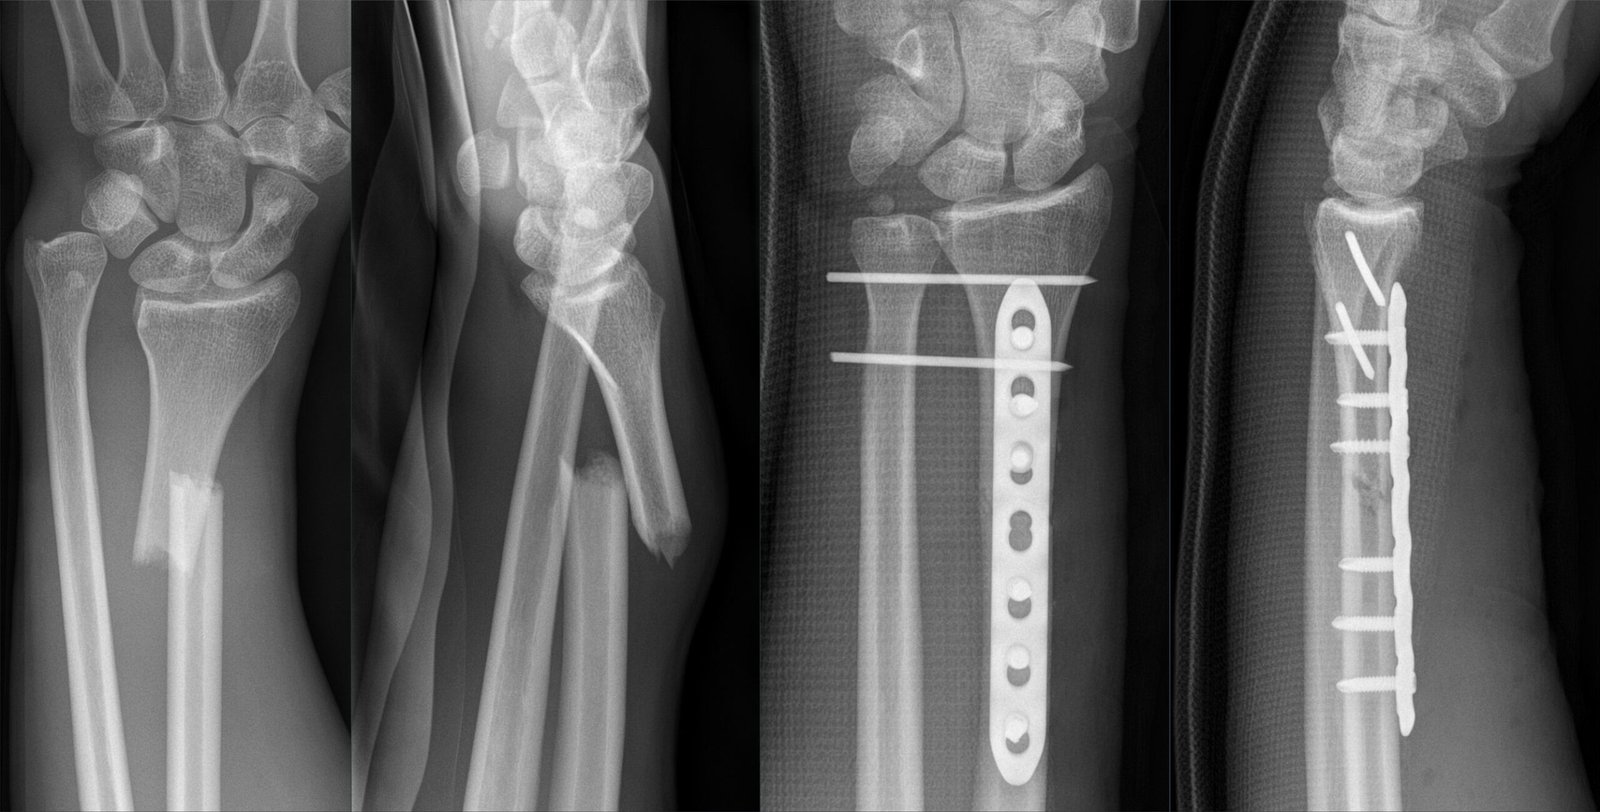

Fracture of radius & Ulna

Galeazi fracture:

Defined as a fracture of the radius with associated dislocation of the distal radio-ulnar joint. A useful way of remembering this type of forearm fracture is with the acronym ‘GFR’ – Galeazzi Fractured Radius.

Radiological features:

1) The radius will commonly be fractured at the junction of middle and distal thirds.

2) The radius will often appear shortened.

3) Carefully assess the distal radio-ulnar joint for widening. 4) On the lateral view, the head of the ulna is usually displaced mali dorsally.

5) There will often be dorsal angulation of the radial fracture.

Manage Galeazi fracture:

1. Analgesia and immobilize.

2. ORIF with DCP plate and screw.

3. Careful follow-up.

4. With late missed injuries, surgical excision of the ulna head can be of benefit.